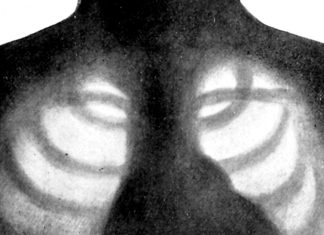

Primeira IA autônoma de análise de raios-X é aprovada na UE

Uma ferramenta de IA (inteligência artificial) que lê radiografias de tórax sem supervisão de um radiologista obteve autorização regulatória na União Europeia na semana passada...